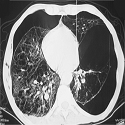

Lung cancer revealed by multiple metastases of the scalp

Mohamed Fetohi, Tarik Namad

PAMJ. 2016; 24: 290. Published 29 July 2016